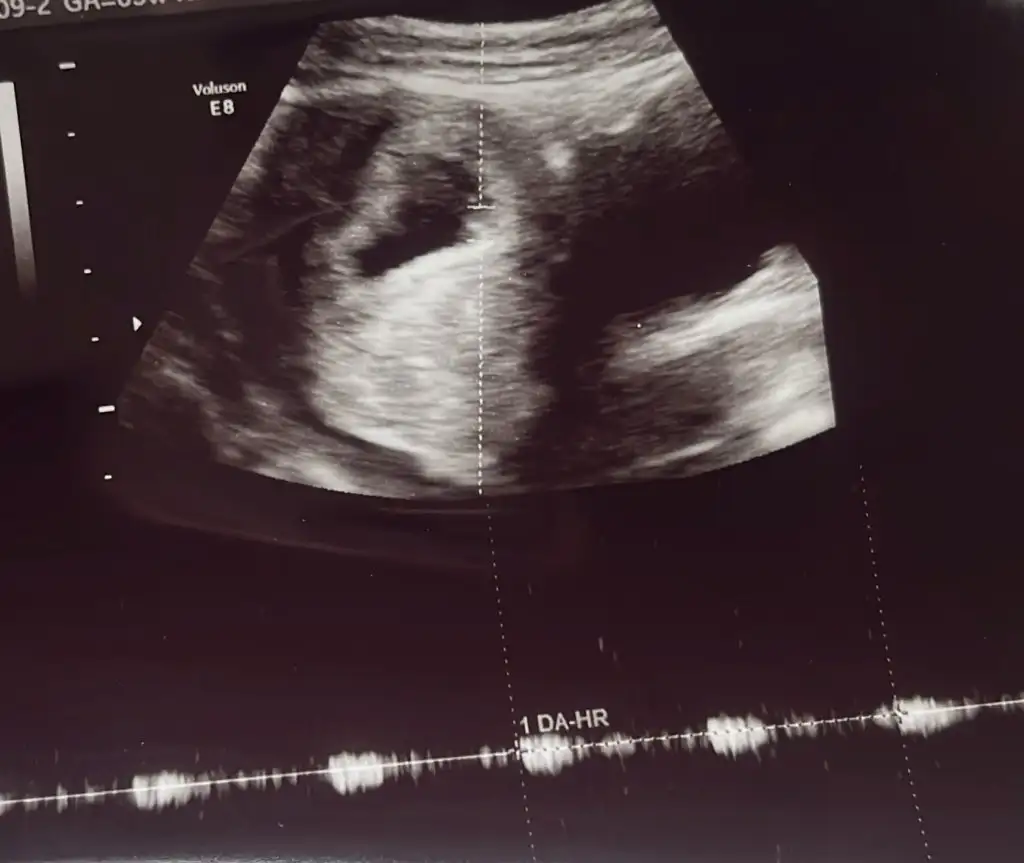

Seninki de kalp şeklinde çıkmış yuvarlak olmadığı için erkek diyeceğimKızlar benim de 5+6 bugğn keseyi görmeye diye gittim kalp atışını kısacık duyduk cinsiyet için yorum yapabilir misiniz

Eki Görüntüle 3425278 Eki Görüntüle 3425279